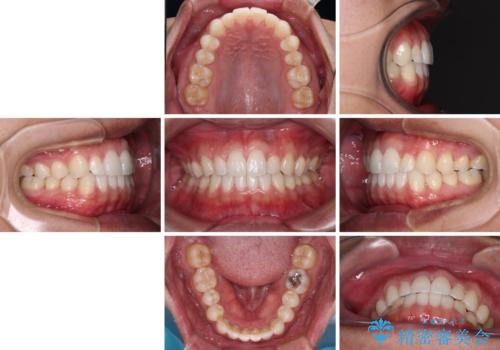

- 前歯のデコボコとクロスバイトを治したいとのことで来院された患者様です。

上下顎ともに歯列全体の側方拡大を行い、下顎前歯はIPR(歯と歯の間を削る)によってデコボコとクロスバイトが解消するように設計し、インビザラインにより治療を行うこととしました。

2年弱で終了する予定でしたが、途中来院されなかった時期があり、その後舌側転位している前歯を動かせるところまで動かしたいとのことで4年ほど治療を継続されました。